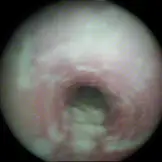

Bronchoskopie

Jede eingehende Lungenuntersuchung sollte eine Bronchoskopie beinhalten. Das Endoskop wird dabei über den unteren Nasengang bis in den Rachenraum vorgeschoben. Über die Öffnung des Kehlkopfes gelangt man in die Luftröhre (Trachea) und kann diese bis zur Aufzweigung in die Hauptbronchien verfolgen. Bei vorhandenem Sekret (Tracheobronchialsekret) kann dieses über einen Entnahmeschlauch im Arbeitskanal des Endoskops direkt entnommen und anschließend untersucht werden. Ist lediglich wenig Sekret vorhanden, kann eine Sekretprobe auch über eine Bronchoalveoläre Lavage (= Spülprobe) gewonnen werden. Hierbei wird eine geringe Menge an Flüssigkeit in die Lunge gegeben und anschließend wieder abgesaugt.